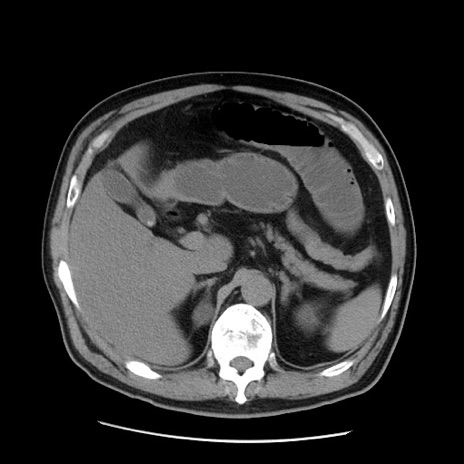

冠状断像

【症例】 60歳代男性

【主訴】 腹部膨満、嘔吐

【現病歴】5日前頃より倦怠感を認め食事量減少し4日前の朝嘔吐、食事摂取困難となった。 3日前近医受診し点滴施行され整腸剤などを処方された。 当日他院を受診し、腹部膨満著明、炎症反応の上昇(CRP10.8、WBC11200)あり、紹介受診となる。

【身体所見】 意識JCS1 受け答えがはっきりしないBP 111/57mHg、 P 67bpm、、BT35.2°C、SpO2 97%(RA)、 腹部:膨隆、打診で鼓音あり、全体的に圧痛有り、腸蠕動音(-)、反跳痛ははっきりせず。

【データ】WBC 11400、CRP 14.20